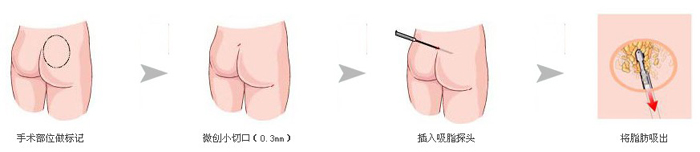

假体隆胸整形手术主要是将假体植入到胸部的部位,使得胸部变得浑圆饱满起来,从而达到了隆胸整形的目的。